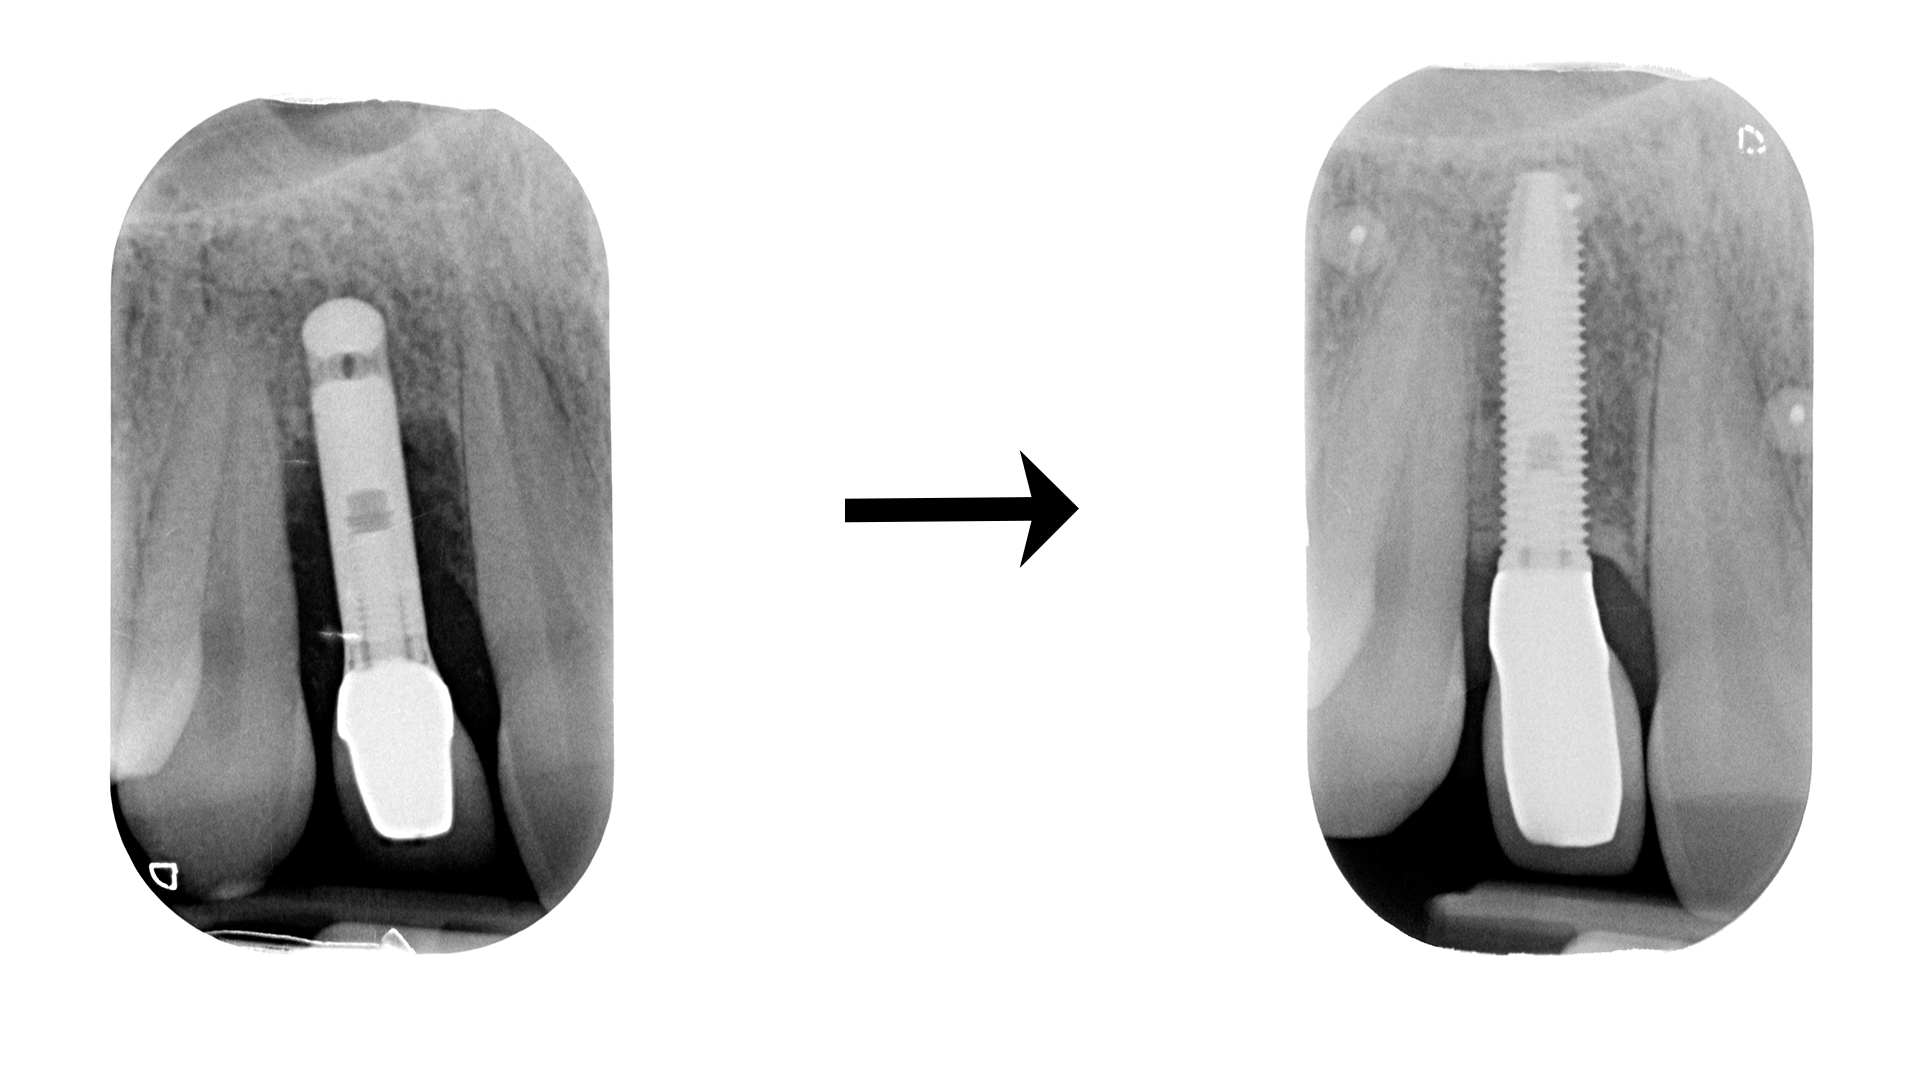

Casi rognosi come questo:

O questo: